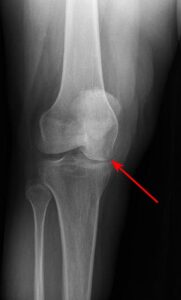

X-ray shows osteonecrosis at the lower end of the femur (thighbone) in the medial femoral condyle.

Imaging techniques play a crucial role in confirming a diagnosis of osteonecrosis.- X-rays: X-rays create detailed images of dense structures like bones. These are often used to identify changes in bone structure that occur during the later stages of osteonecrosis. However, in the early stages of the condition, X-ray results typically appear normal, which may necessitate additional imaging for accurate diagnosis.

X-ray shows osteonecrosis at the lower end of the femur (thighbone) in the medial femoral condyle.As osteonecrosis progresses, narrowing of the joint space can occur due to loss of articular cartilage.